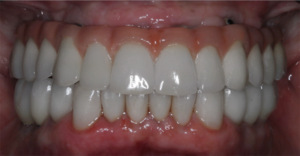

Figura 6 – Aspecto intraoral em oclusão da reabilitação final dos arcos superior e inferior em cerâmica. Próteses confeccionadas pela Dra. Joraci Teixeira.